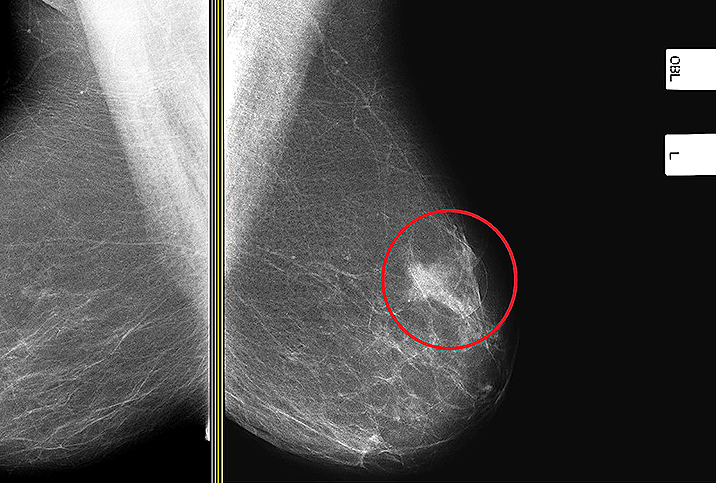

Dense tissue can put women at a higher risk for breast cancer over the course of their lives.